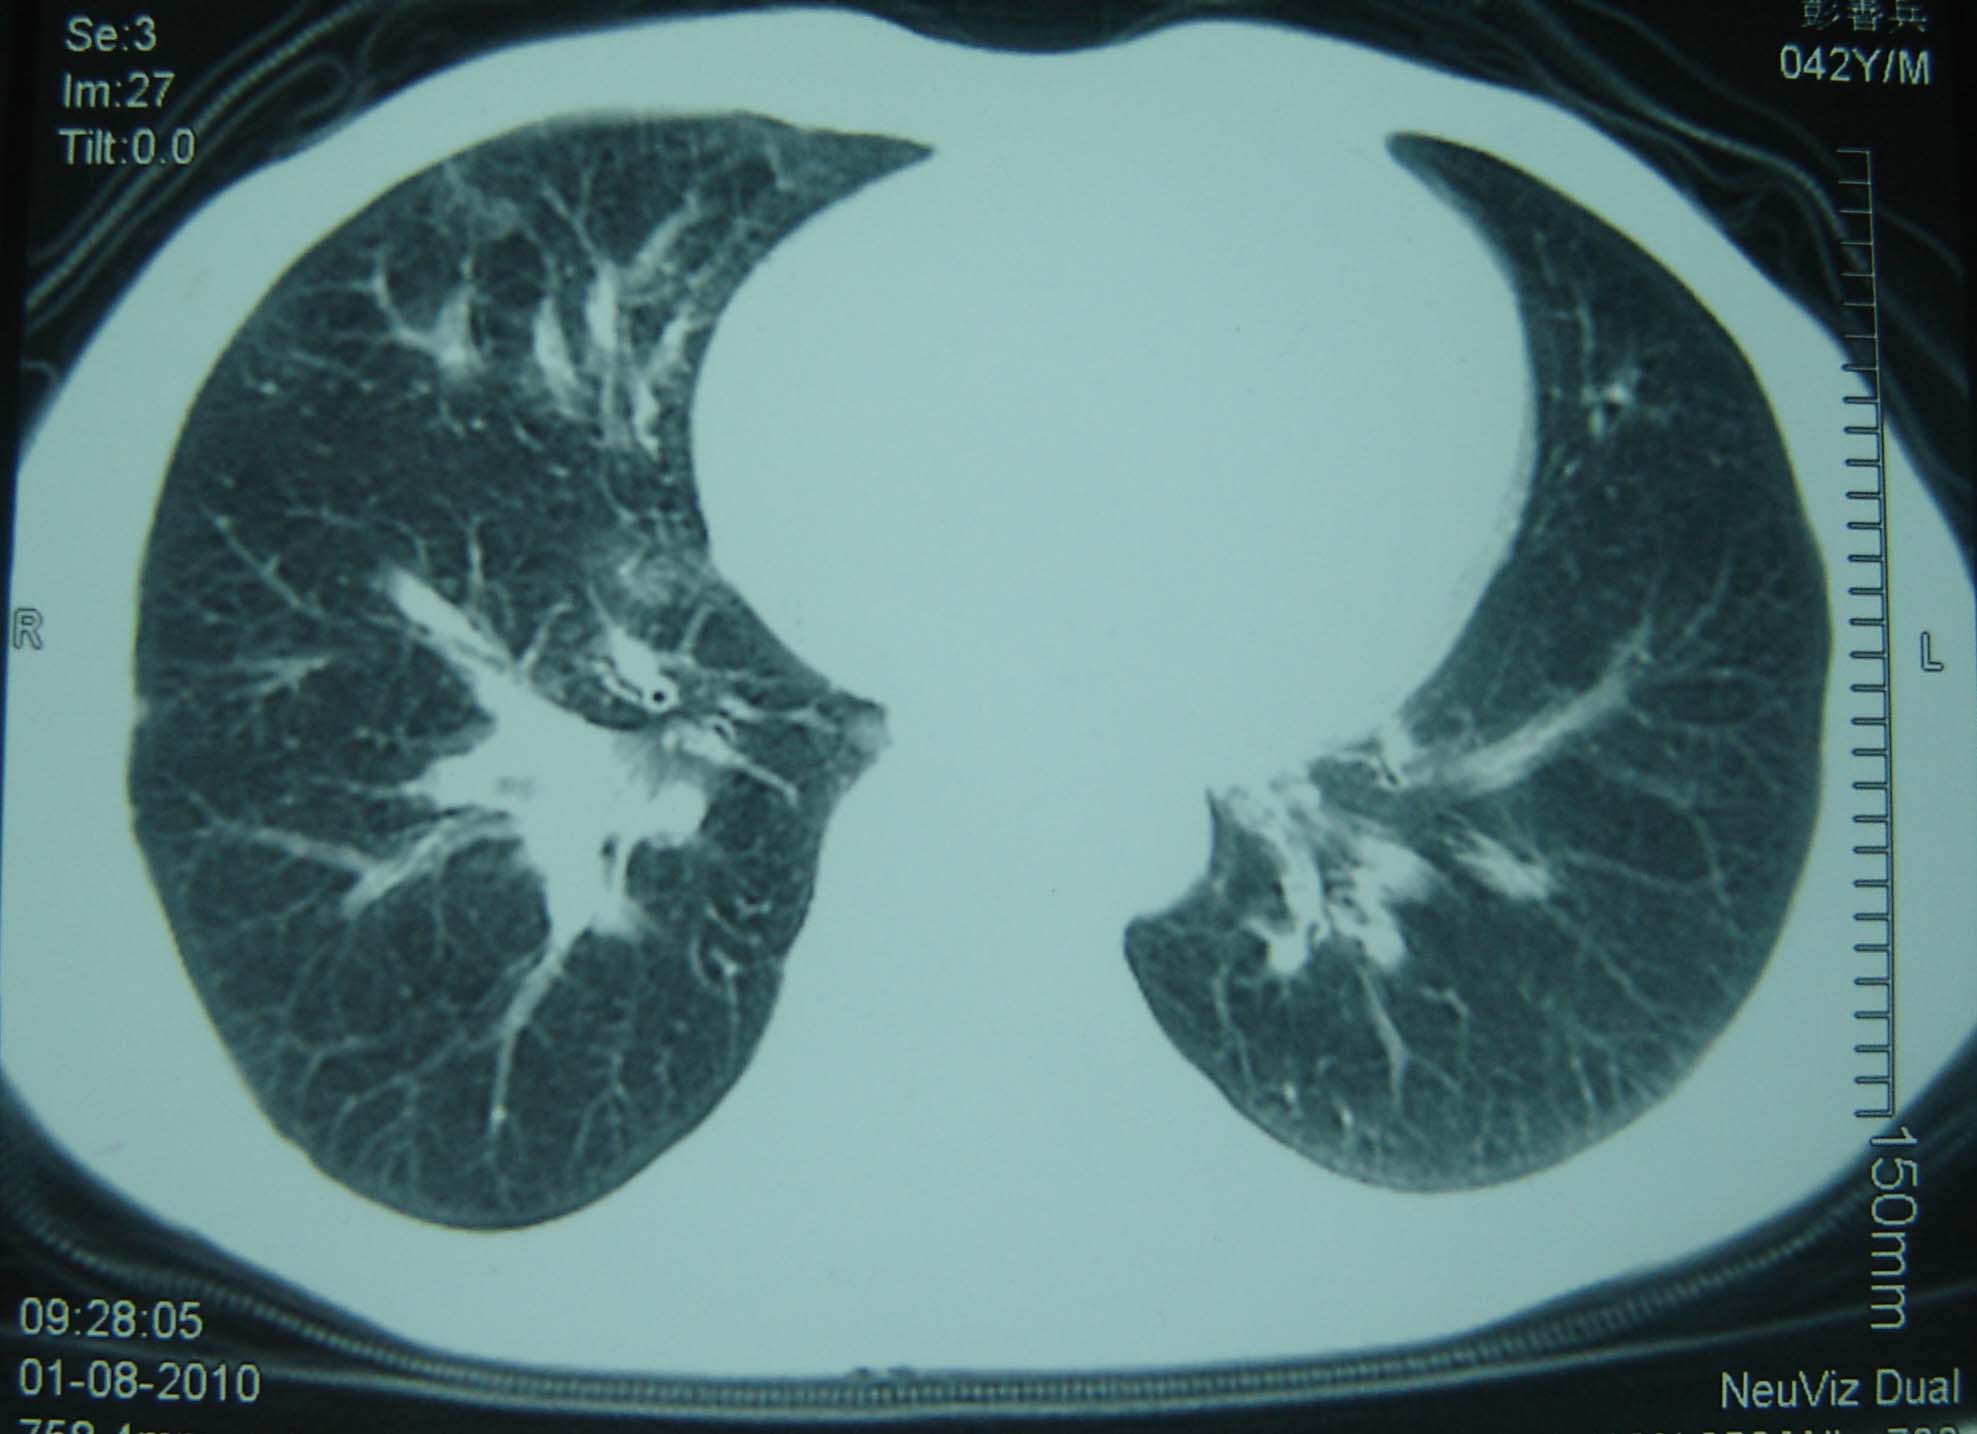

标题: CT25321:两肺多发结节 请会诊 [打印本页]

标题: CT25321:两肺多发结节 请会诊

男 、43岁,咳嗽胸痛,装修工,平时接触粉尘较多,有吸烟史10多年,纤维支气管镜检查未发现异常,胃镜、腹部b超检查亦未发现异常,颈部淋巴结活检未发现肿瘤细胞。

不能排除转移,如果不能找到原发灶,只有短期随访。

结节病?转移瘤?

结节病。

转移瘤?

1)考虑双肺及胸膜多发性转移瘤。2)肺气肿。

双肺结节病。